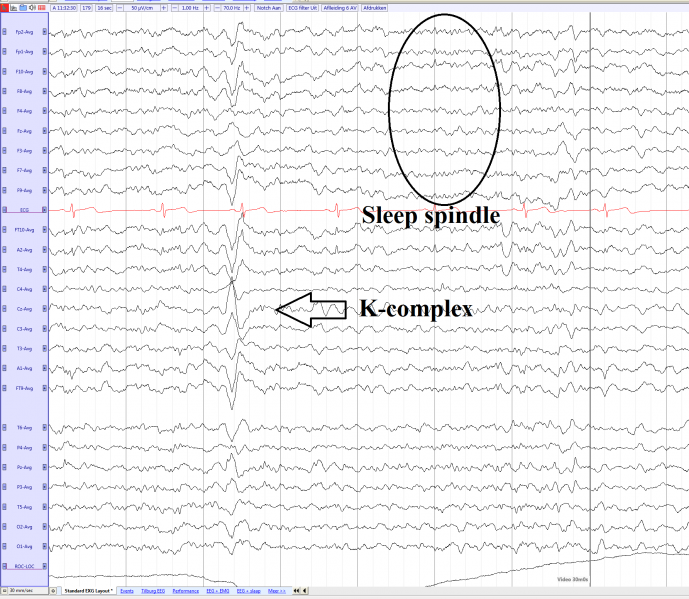

Diphasic K-complex with a maximum at Cz in non REM 2 sleep

| current | 13:50, 3 April 2017 | 1,785 × 1,553 (198 KB) | EEGpedia (Talk | contribs) | Diphasic K-complex with a maximum at Cz in non REM 2 sleep |